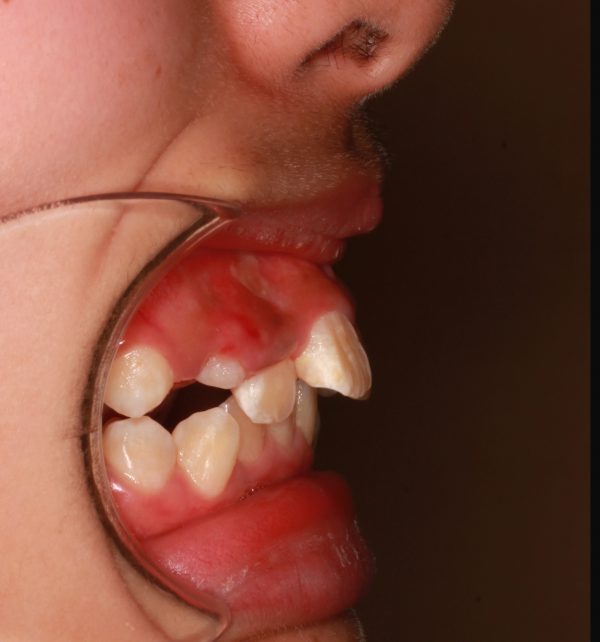

前歯の段差が激しく、”八重歯”の状態です。

前歯が前に傾斜しているため

”出っ歯”も気になるとの事です。

叢生を伴う 上顎前突症 です

矯正治療のために 上下左右の 抜歯を行い

段差を解消し、前歯を後方に移動させました。